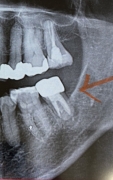

写真は歯科で切開したあと、家で撮りました。

クラウンの横のところが腫れています。

画像1

歯が弱っているというより、添付された写真から察するに、歯を支えている ( た ) 骨が弱っているものと推測します。